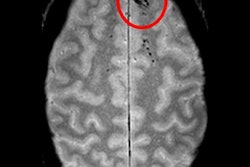

Cerebral microbleeds are small focal hemorrhages in the brain that are prevalent in stroke, neurodegenerative disorders, traumatic brain injury, and after radiation therapy, Chen said. The microbleeds are visible on susceptibility-weighted imaging (SWI), a high-resolution, T2-weighted MRI technique that uses phase information to increase contrast. However, traditional detection and labeling of cerebral microbleeds requires manual inspection of 3D SWI volumes and is labor-intensive.

Current automated methods developed to tackle this challenge have a high false-positive rate that limits their practical value, Chen said. A previous computer-aided detection (CAD) method developed by UCSF researchers was able to detect cerebral microbleeds at 86% sensitivity, but it also provided many false positives. Inspired by the recent success achieved with deep CNNs, the researchers sought to utilize a 3D deep residual network to eliminate many of these false-positive findings.

In testing, the CNN yielded 95% sensitivity and 72% precision. It also eliminated 88% of the false-positive results found with the group's previous CAD system. What's more, the sensitivity and rate of 0.39 false positives per cerebral microbleed detected outperformed other methods reported in the literature, according to the researchers.